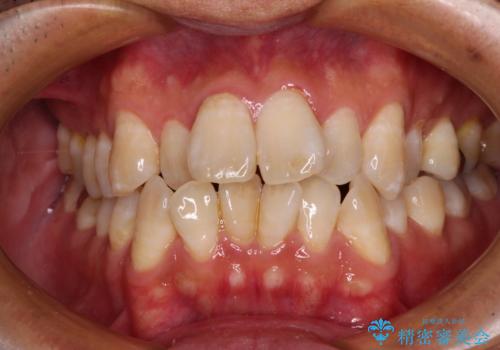

[ 総合歯科診療 ] がたつきの改善とセラミック治療

![[ 総合歯科診療 ] がたつきの改善とセラミック治療の症例 治療後](https://seimitsushinbi.jp/wp/wp-content/uploads/2024/03/7212917eb9c4ef33050c52e7f9724490-500x350.jpg?v=1710833188)